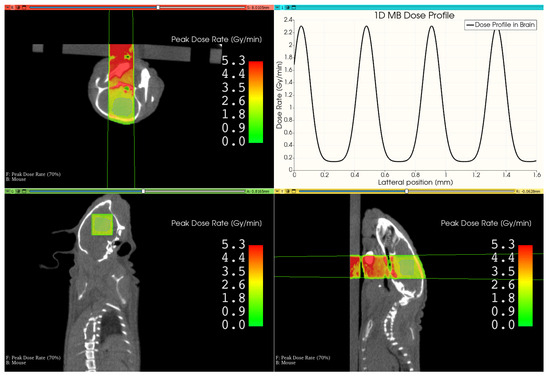

3.3. Therapy Plan for a Mouse Treatment

3.4. Histological Section of an Irradiated brain